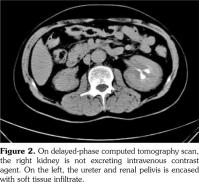

A 51-year-old male patient admitted to our outpatient clinic with complaints of flank pain and fatigue. He had a history of renal stones and peripheral arterial disease. He had a medically unmanageable hypertension. Blood pressure was 200/110 mmHg. Serum creatinine level was 1.2 mg/dL. He was evaluated with contrast- enhanced multislice computed tomography. Along with small calyceal stones, there was bilateral, quite symmetrical perinephric ''rind-like'' soft tissue infiltration. Right kidney was atrophic but still functioning without pelvicalyceal contrast excretion. The soft tissue infiltration obliterated both renal hila and caused proximal ureteral stenoses with mild calyceal dilation on the left side (Figures 1 and 2). Distally, the ureters were normal. Incidentally, abdominal aorta, common iliac arteries, proximal celiac trunk, and proximal renal arteries were noticed to appear “coated” with subtle perivascular tissue infiltration. An endovascular aortoiliac stent-graft was in place. He rejected any further diagnostic intervention after he presented with a blood creatinine of 2.2 mg/dL. He underwent an unenhanced computed tomography examination with the same findings before. Renal scintigraphy revealed a non-functioning right kidney. Perinephric soft tissue infiltration was considered as the differential diagnosis of ECD. Direct radiographies of the extremities were obtained. All of the long tubular bones showed diametaphyseal cortical and patchy medullary sclerosis reinforcing the diagnosis of ECD (Figure 3). The patient underwent right nephrectomy for the control of hypertension and a double-J stent was placed on the left side for the relief of ureteral obstruction. The nephrectomy specimen showed the typical histological features of ECD. Serum creatinine level dropped to the borderline values after the operation and his blood pressure was in the normal range with medications. The pathological analysis of the nephrectomy specimen revealed an inflammatory infiltrate formed by foamy histiocytes that were positively stained for CD68 and neutrophilic aggregates which confirmed the preoperative diagnosis (Figures 4 and 5). A written informed consent was obtained from the patient.

The X-ray changes that are considered to be pathognomonic and found in almost all patients are dia-metaphyseal osteosclerosis bilaterally and symmetrically in the tubular bones of upper and lower extremities.(5) They also show an increased uptake of tracer on Technetium 99m bone scintigraphy.(4) These bone changes may be misdiagnosed as Paget’s disease, lymphoma, sarcoidosis, metastases, or lipid storage diseases.(6,7)

In our case, computed tomography findings suggested retroperitoneal fibrosis but the infiltrate did not involve the vena cava and the paraaortic infiltration was circumferential instead of sparing the posterior aspect of the aorta. Also, the perinephric infiltration was far more striking than the perivascular space which is inconsistent with retroperitoneal fibrosis. Therefore, the differential diagnosis consisted mainly of processes involving perinephric and perivascular spaces, namely, lymphoma, retroperitoneal fibrosis, and ECD. The diagnosis of ECD was strongly suggested with the radiographic findings of the extremities which revealed symmetrical dia-metaphyseal osteosclerosis.